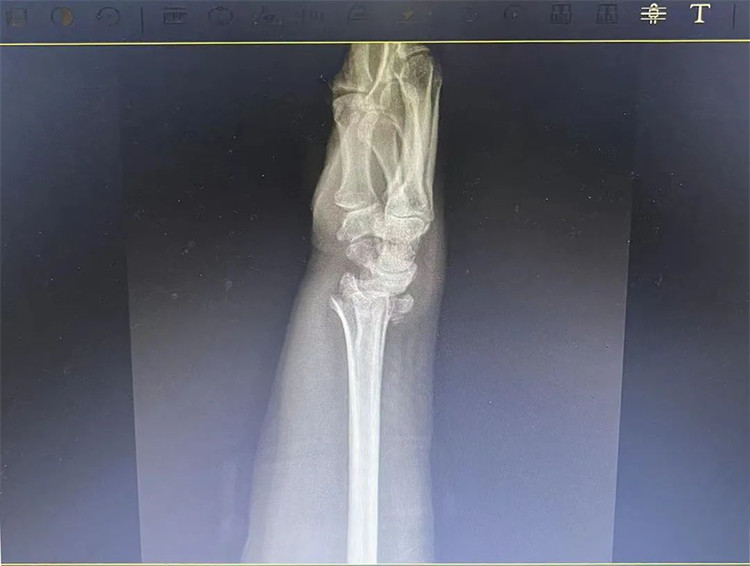

患者基本情況

患者老年女性,50多歲,在騎電動車停下時因電動車倒下,右手著地,當(dāng)即感覺,右腕及骶尾部腫痛伴右關(guān)節(jié)畸形、活動受限,急來我院就診。門診醫(yī)師結(jié)合病史、查體及輔助檢查后,診斷為:右橈尺骨遠(yuǎn)端骨折、骶尾部挫傷并收入住院部。